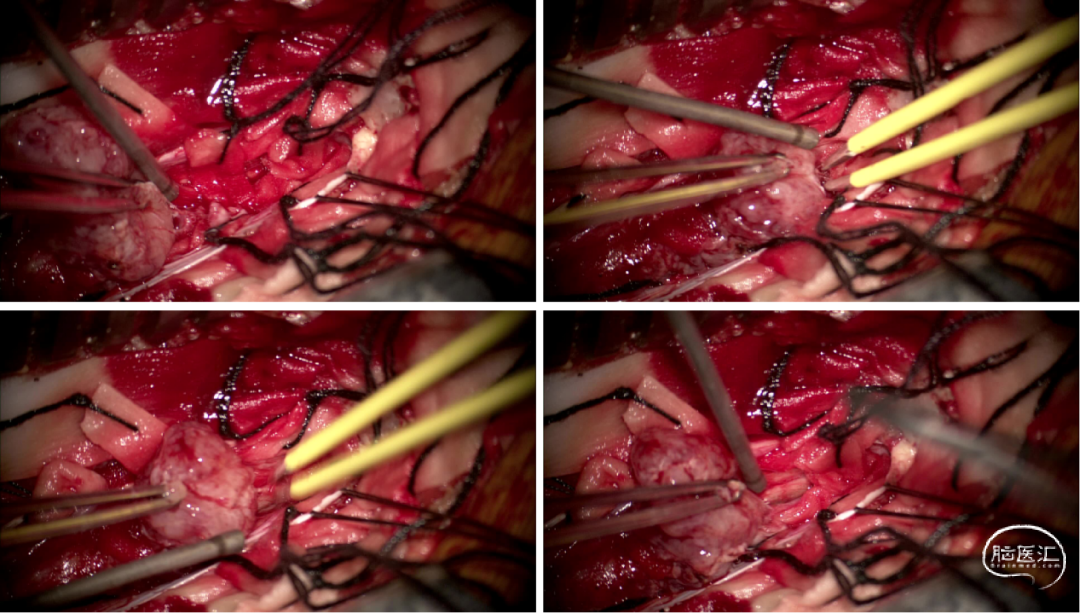

手术情况

硬脊膜张力高,脊髓向背侧膨出,与脊髓腹侧粘连紧密,肿瘤挤压脊髓,肿瘤边界分离,减少对胸髓的牵拉,降低了术后患者神经功能发生的概率,术后患者肢体麻木症状改善。